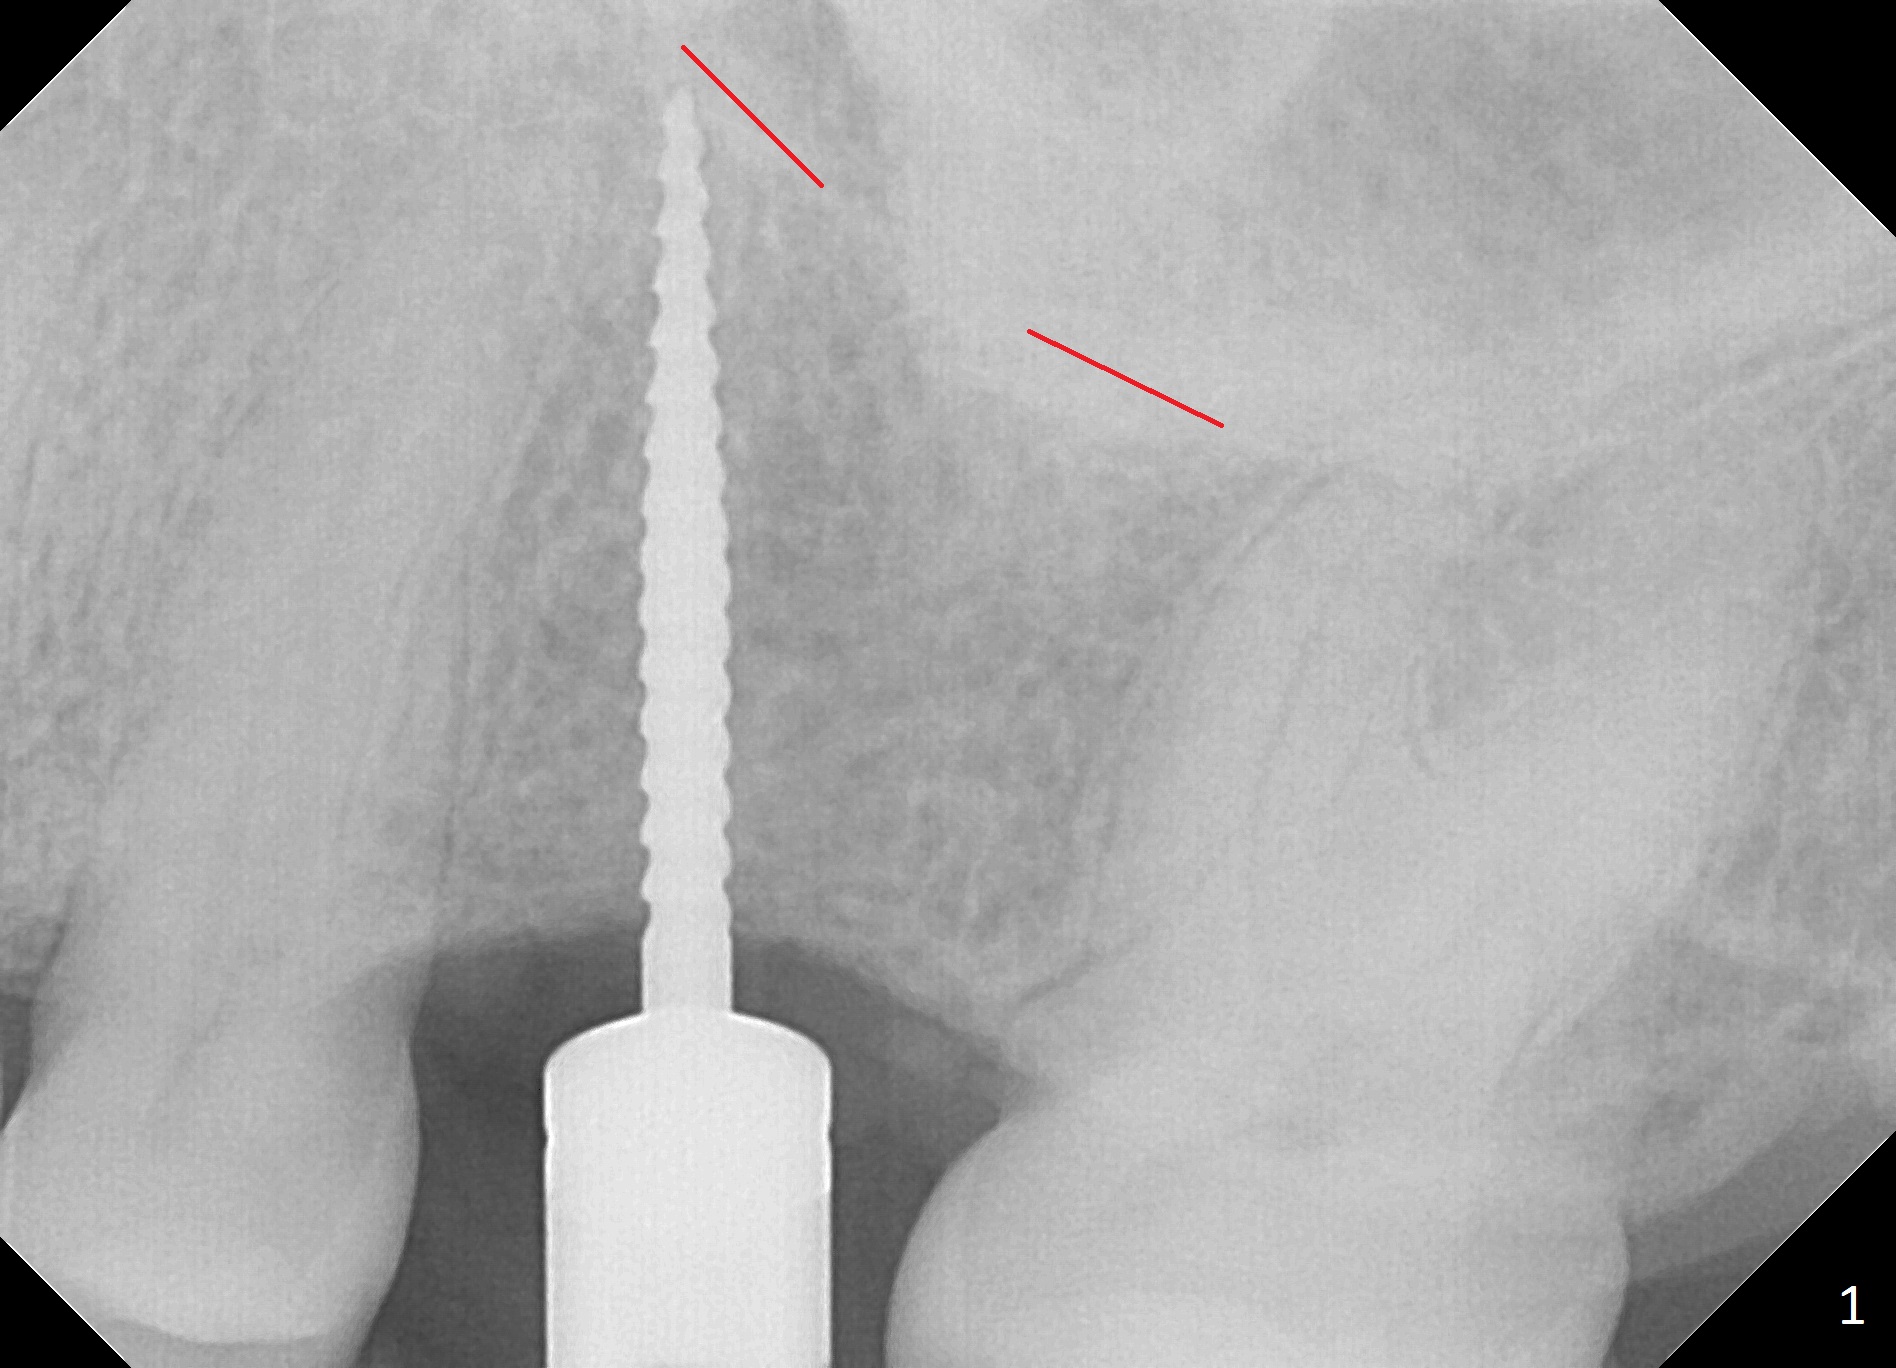

The edentulous area at #14 is moderately atrophic, After incision, the bone is too hard for #15 blade for bone expansion. Osteotomy is initiated with 1.2 mm drill, followed by insertion 1.3/2.3 mm bone expander (Fig.1). Use the same instruments are reused twice to change the trajectory (Fig.2,3). Finally Lindamann bur is utilized to move the osteotomy distally by ~ 2 mm; bone expansion continues until 2.4/3.7 mm expander for 13 mm with 50 Ncm (Fig.4). The last expander 3/4.4 mm barely enters the osteotomy for 6 mm. A 3.7 mm drill has to be used for 12 mm before placement of a 4.5x11.5 mm implant with >35 Ncm (Fig.5). A 5.5x5(3) mm abutment is placed with allograft (<) placed around the implant. Following suturing, periodontal dressing is applied around the implant. The abutment dislodges 3 months postop (Fig.6). Crown is delivered 3 weeks later. The abutment screw is retightened ~ 2 months later. He is a bruxer. The abutment screw is loose again <2 years post cementation (6 months post #18 screw retightenting and occlusal reduction), probably related to distal implant placement (Fig.7).